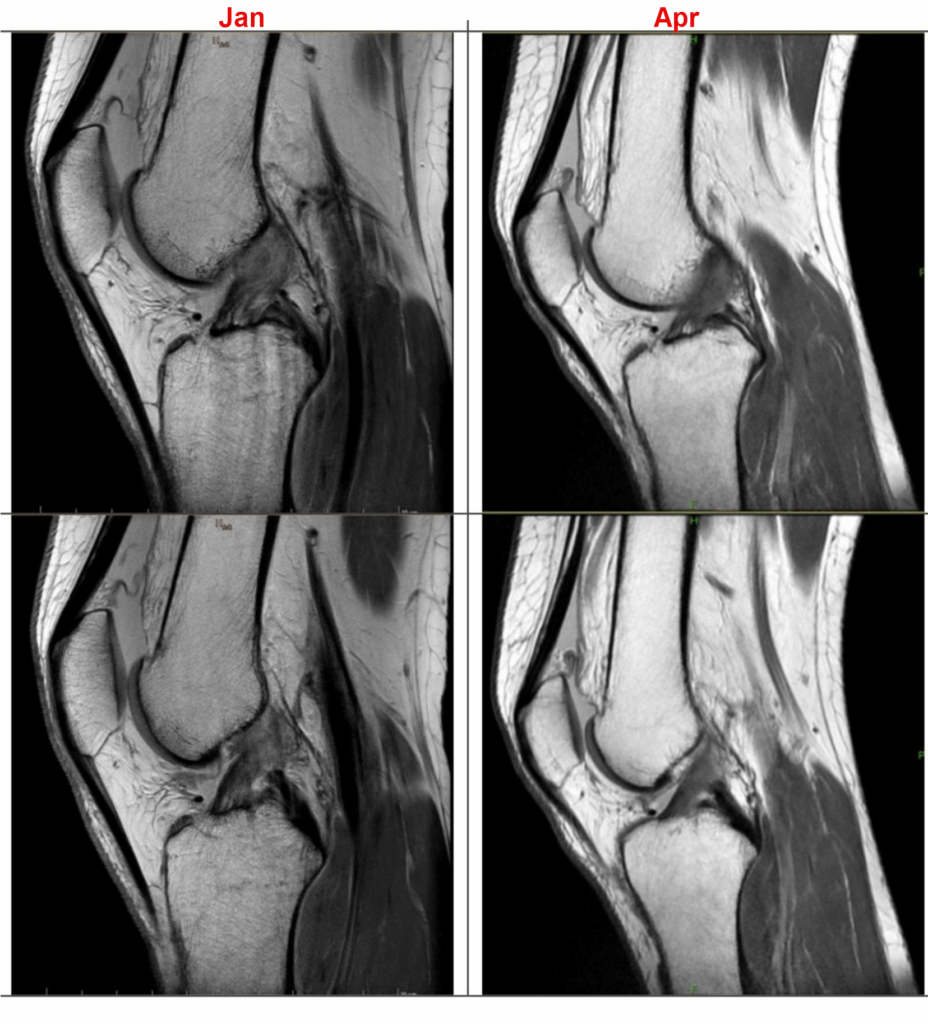

By the end of April, I had gotten my MRI images back.

There is intermediate signal at the posterior aspect of the ACL with indistinct morphology of the fibers, overall improved from previous exam. There is no redundancy, discontinuity, or fluid filled defect to confirm presence of a full-thickness tear

From the Radiologist’s MRI Report

There appears to be a healing process all around which is great news.

PM&R doctor’s note about the MRI findings

Yes, great news indeed😊. The vindication was finally real.